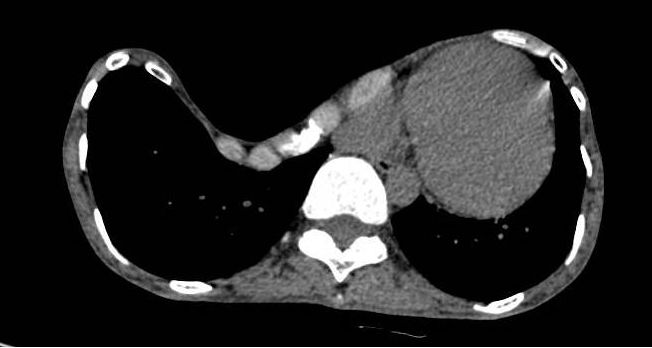

入院后,小明的检查结果比预想的更加严重。胸部CT可见患者的前胸壁已经接近脊柱水平,也就是俗话说的“前胸贴后背“,报告显示:扁平胸合并漏斗胸,Haller指数达到了惊人的25.0。肺功能显示:极重度限制性通气功能障碍。心脏超声可见:轻度三尖瓣返流。心电图可见:不完全右束支阻滞。凹陷的胸壁已经严重压迫到了心肺,导致了心肺功能的异常,若不手术治疗,对小明造成影响会越来越严重。